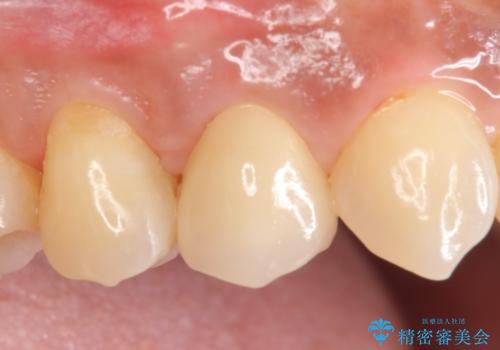

右上4は根管治療を行い、オールセラミッククラウンによる補綴を行いました。

今回用いたオールセラミッククラウンはジルコニアフレームという白い素材の上にセラミックを盛っているため、審美性が非常に高いのが特徴です。

また、ジルコニアは人工ダイヤモンドの材料にも使われているほど高い強度を持っており、そのためオールセラミッククラウンは審美性だけでなく、奥歯やブリッジの補綴も可能とするクラウンです。